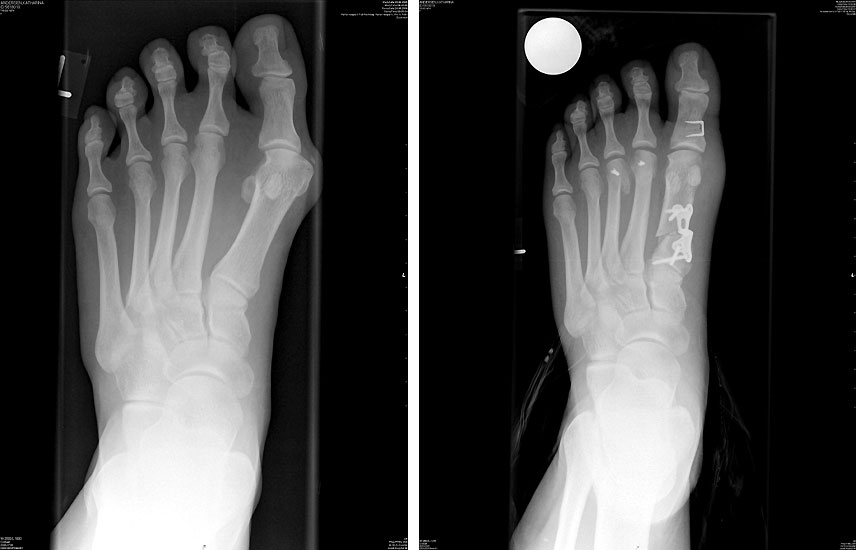

• Röntgenaufnahmen des Fußes in 2 Ebenen, a.p. stehend

• Winkelstabiles Implantat (z.B. TOM Platte der Firma Wright Medical).

Die OP Methode hat sich als Standardeingriff bei größeren Hallux valgus Fehlstellungen etabliert. Der Intermetatarsale Winkel kann sehr gut korrigiert werden. Der Erste Strahl wird stabilisiert und kann wieder Last aufnehmen. Die Verwendung einer winkelstabilen Plattenosteosynthese zur Fixation einer proximalen Osteotomie am MT 1 hat sich bereits bewährt123, insbesondere auch mit der hier verwendeten TOM Platte (Thomas M. 2009). Die V-förmige Knochenschnittführung bietet eine zusätzliche Stabilität.

Häufig wird additiv eine Akin Osteotomie durchgeführt. Irritationen über der tastbaren Platte führen in vielen Fällen zur Metallentfernung. Eine Studie zur Auswertung der Ergebnisse wurde begonnen.